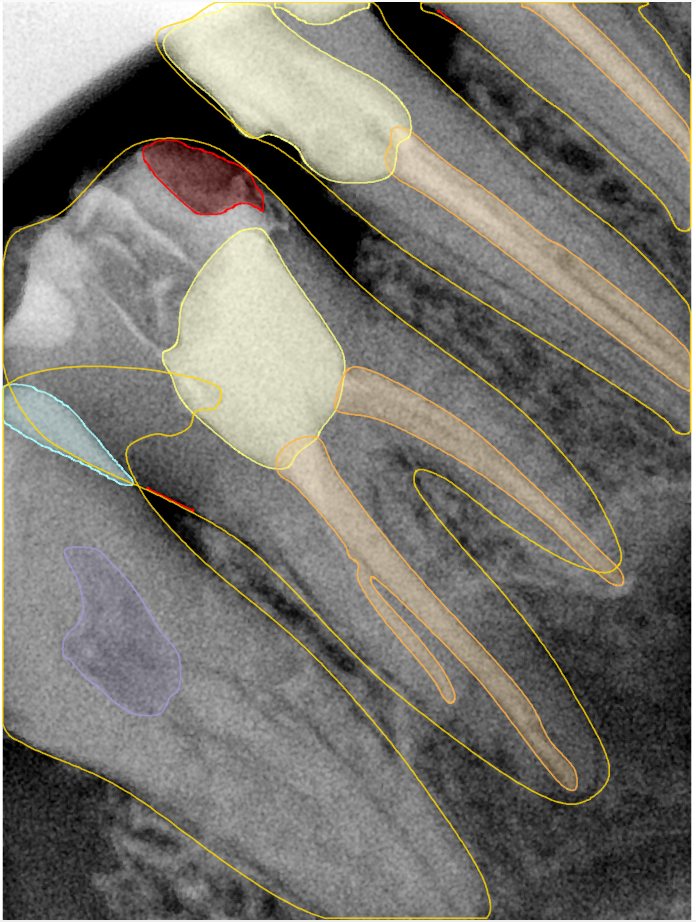

CR/DR 牙齿分割阶段记录

当前进展

- 完成了 CR/DR 牙齿相关分割训练

- 当前结果已经达到阶段预期,但仍有细节问题需要继续处理

相关测试

遇到的问题

- 训练过程中出现过 mask 下移问题

- 部分结果会出现 box 填充异常

- mask 边缘仍然有比较明显的锯齿感